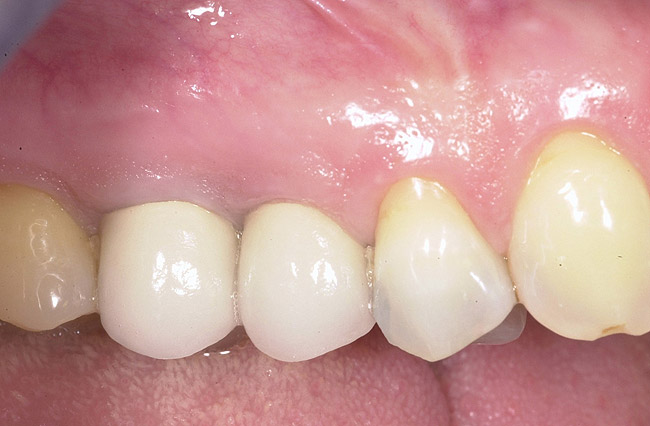

Figure 9  Final implant-supported restoration.

Figure 9